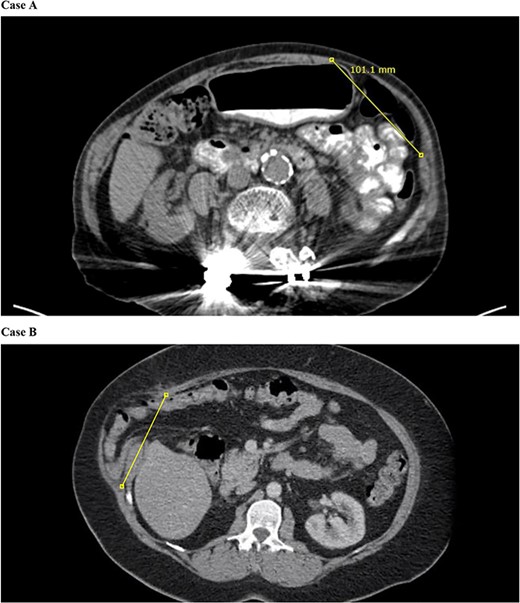

Initial laparoscopic survey demonstrated separation of the linea semilunaris from the internal oblique and transversus abdominis. The peritoneum on the left side was opened to allow better exposure of the muscle. Starting inferiorly just off the edge of the anterior superior iliac spine, we approximated the linea semilunaris to the internal oblique using a # 1 barbed synthetic absorbable monofilament suture (StrataFix™ PDS™; Ethicon, Somerville, NJ) running the suture in cranial direction. Thereafter, we reversed the direction of the suture to return running the suture in caudal direction prior to cutting the stitch. This noticeably decreased the bulge in her left upper quadrant (Fig. 2A). Length of this abdominal wall defect measured intraoperatively was 8–10 cm.

Barbed synthetic absorbable monofilament suture was used to approximate the linea semilunaris to the internal oblique.